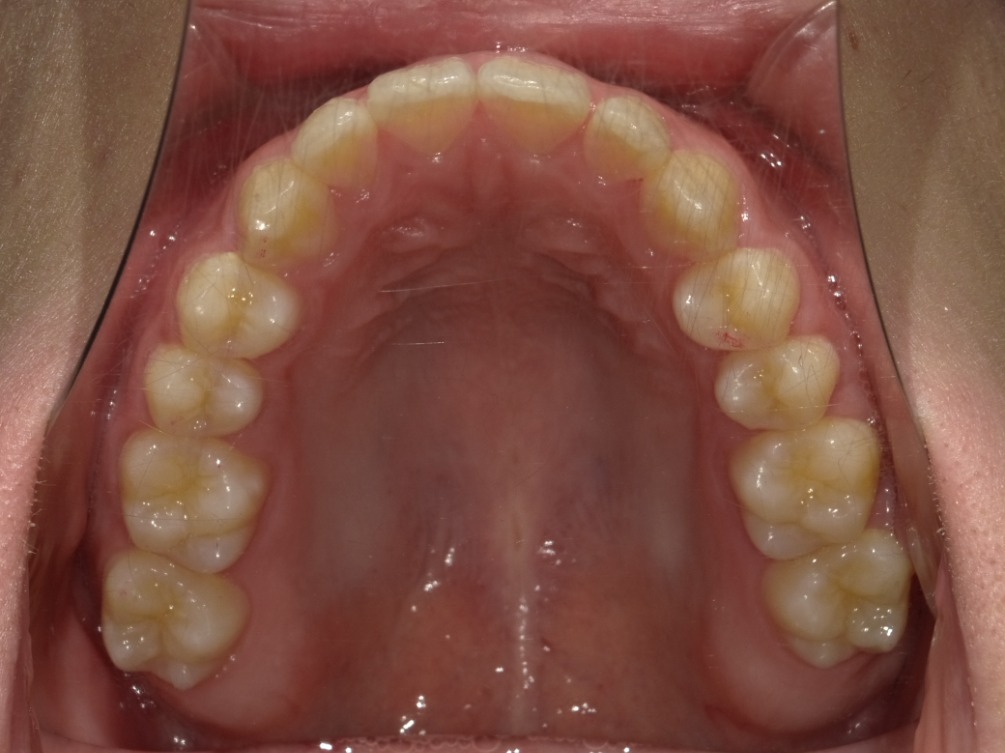

上顎

| 治療内容 | インビザライン 全顎 |

| 治療詳細 | 反対咬合や叢生を整えるために、歯の表面にアタッチメント(白い突起)をつけ、IPR(歯と歯の間を削る)を行いました。 また、顎間ゴムと呼ばれる上顎と下顎に渡って引っ掛けるゴムの補助装置も用いて治療を行いました。 |

| 患者情報 | 10代 男性 デンタルモニタリング使用 |

| 主訴 | 下顎が前に出ている(受け口) 歯のがたつき |